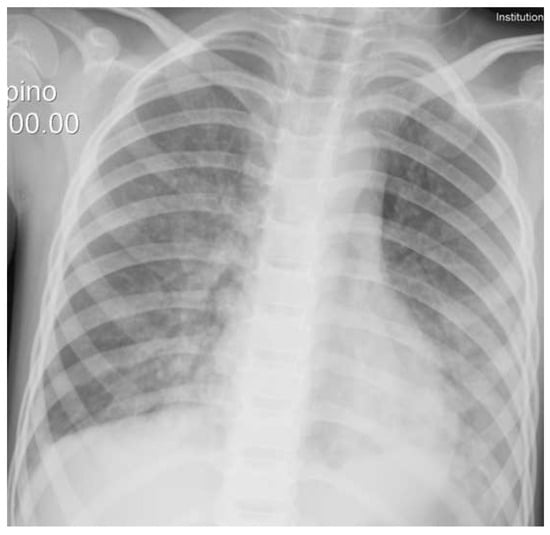

He reported that some water had entered the mask and that he had not been able to remove the device. At evaluation in the ED, he presented tachypnea (36 breaths/minute), dyspnea with nodding and indrawing, hypoxia (peripheral oxygen saturation was 82%), and respiratory acidosis (pH 7.29, pCO2 44 mmHg, HCO3 20 mEq/L, and BE −4.9). A chest X-ray showed bilateral thickening of the lungs’ interstitial tissue (Figure 2). He was transferred to the intensive care unit, receiving high-flow oxygen therapy for 24 h. He fully recovered uneventfully in the following days.

Figure 2. Chest X-ray showing bilateral thickening of the lungs’ interstitial tissue.